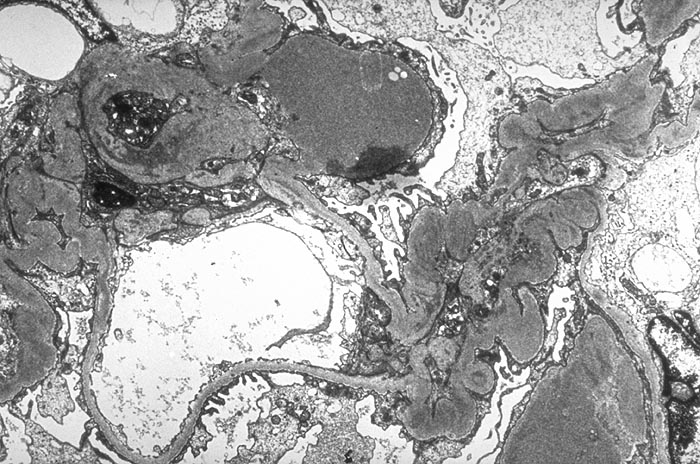

PathoPic – image database / PathoPic ID 2690 - Membranoproliferative Glomerulonephritis: mesangiale Depots

Membranoproliferative Glomerulonephritis: mesangiale Depots

Massive überwiegend mesangiale Depots. Die peripheren Glomerulusschlingen sind wenig verändert.

Keine IgA Nephritis.

Depots hauptsächlich subendothelial, in späteren Phasen auch mesangial, gelegentlich einzelne subepitheliale Depots. Wenn viele subepitheliale Deptos vorliegen=Typ III.